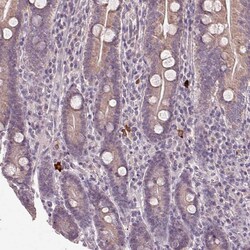

- Immunohistochemical analysis of NKG2E in human small intestine using NKG2E Polyclonal Antibody (Product # PA5-64033) shows strong cytoplasmic positivity in a subset of lymphocytes.